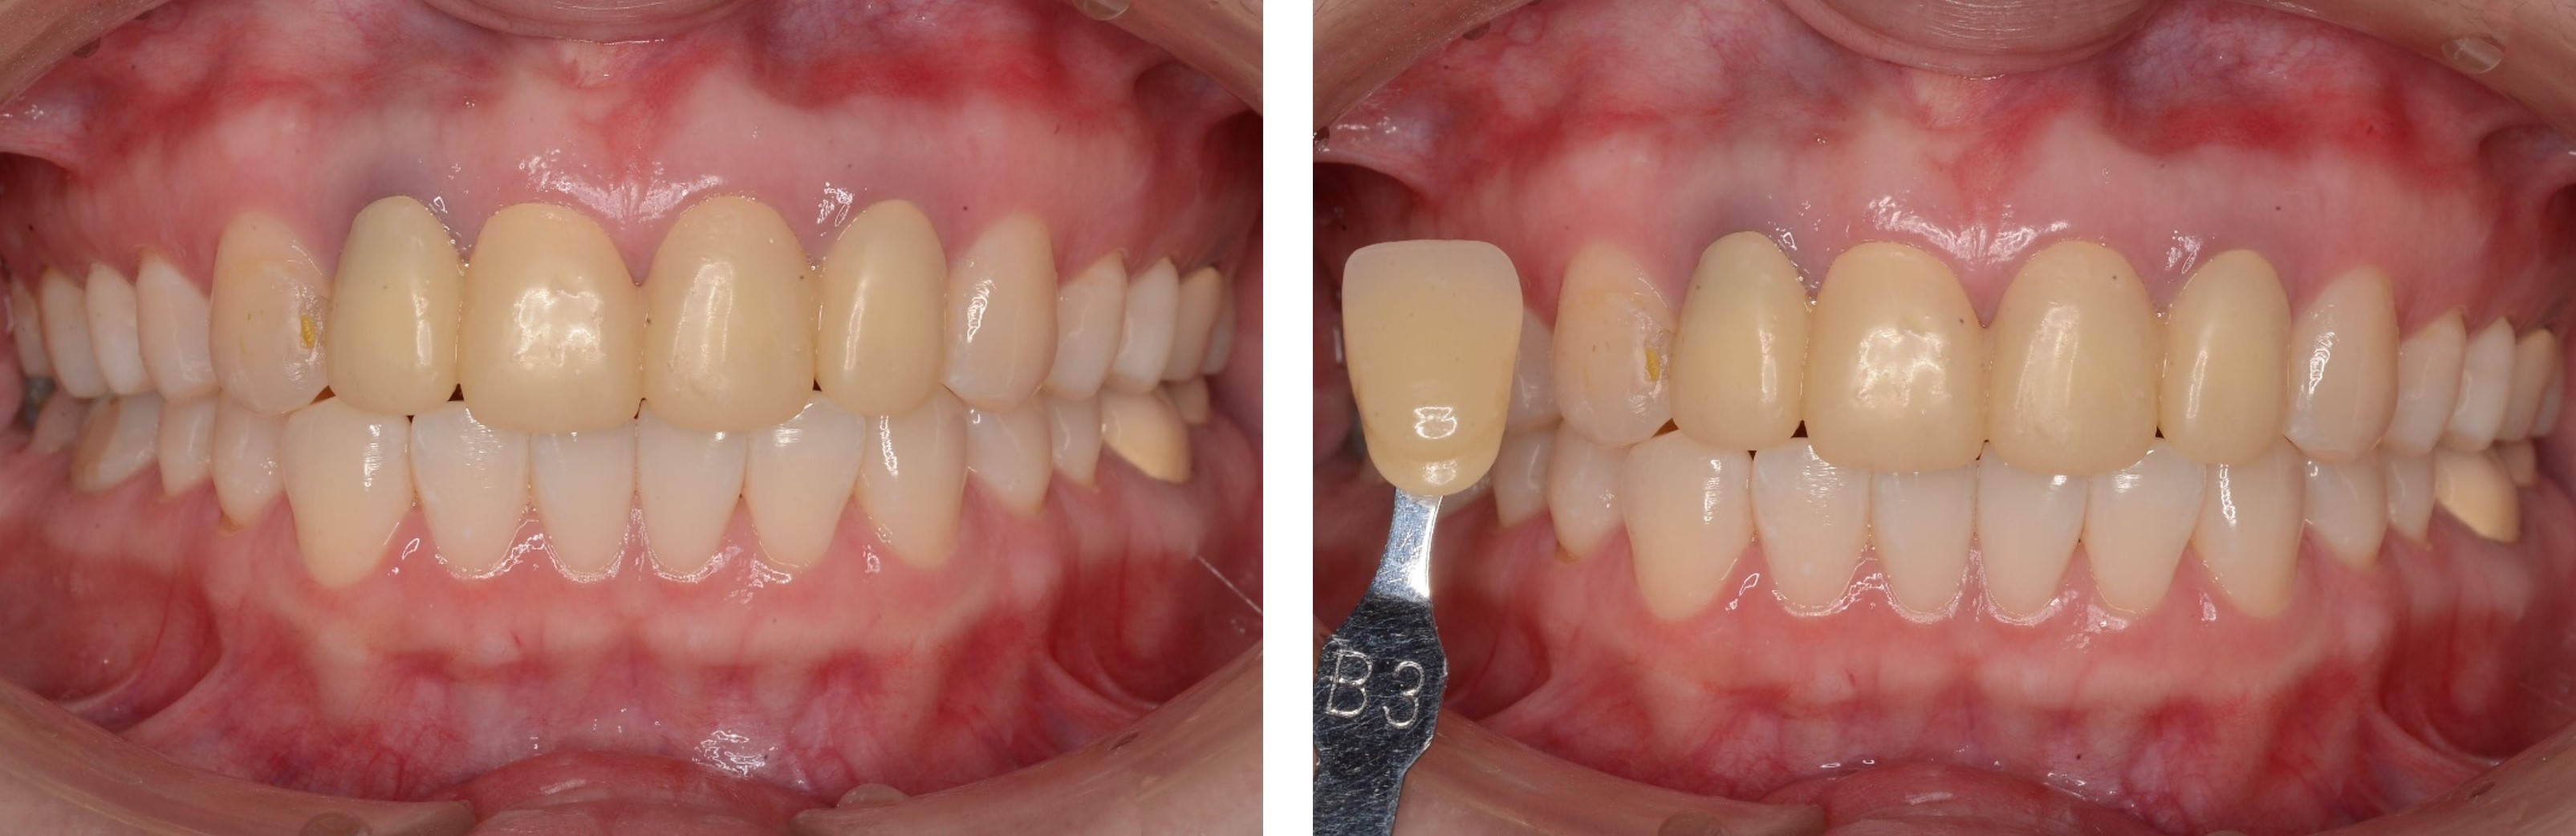

美白前,牙齒預比色-B3

美白前,微笑分析

居家美白1個月後再評估-A1